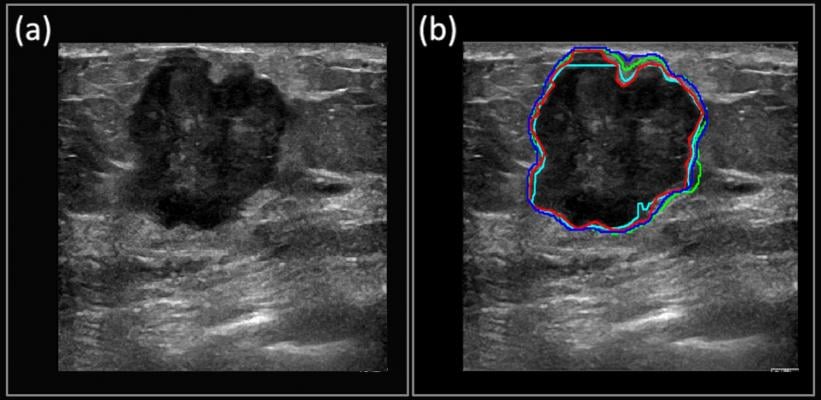

The red outline shows the manually segmented boundary of a carcinoma, while the deep learning-predicted boundaries are shown in blue, green and cyan. Copyright 2018 Kumar et al. under Creative Commons Attribution License.

For the past few years, Kumar has been leading an effort to use GPU-powered deep learning to more accurately diagnose cancers sooner using ultrasound images. The work has focused on breast cancer (which is much more prevalent than ovarian cancer and attracts more funding), with the primary aim of enabling earlier diagnoses in developing countries, where mammograms are rare.

Read Kumar’s paper, “Automated and real-time segmentation of suspicious breast masses using convolutional neural network.”